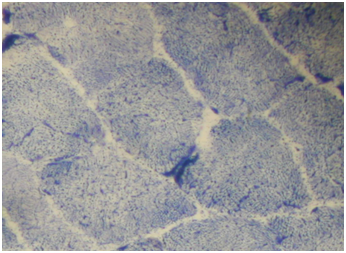

Routine histological analysis of the quadriceps or deltoid muscle specimen of all cases showed mild variation of fiber size with interspersed mildly atrophic fibers (Figure 1). The abnormal variability of fiber size with type I fibers predominance was clearly demonstrated in Figure 2 and were seen in cases no. 1,4 &5. The histochemical examination of the muscle biopsies of all patients revealed marked reduction in ACHE activity (Figure 3). There was increased oxidative enzyme NADH reaction at the neuromuscular junction in all cases but case no. 3 (Figure 4).  Table 2 shows the characteristics of the histochemical changes in six myasthenia gravis patients. The histological pictures in all cases showed almost common features of the following: minimal muscle fiber variation in size even in cases with long standing myasthenia gravis, and showed occasional atrophied fibers. In three of the six patients, predominance of type I fibers were observed, the atrophied fibers tended to be of type II. The most consistent finding in all cases was marked reduction in AChE staining at the end plates, However, increased NADH at the end plate were seen in five of the six patients. None of the cases showed lymphorrhagia that had been described before. In three of the six patients, electron microscopy was performed. In two of three cases mild increase in glycogen was noted and in one case, glycogen increase was coupled with increased fat globules.

Figure 1 Quadriceps muscle biopsy of patient 1. Hematoxyline and eosin sections showing variation in fiber size with interspersed mildly atrophic fibers. The atrophic fibers are seen selectively in type II fibers (Mag.400x).